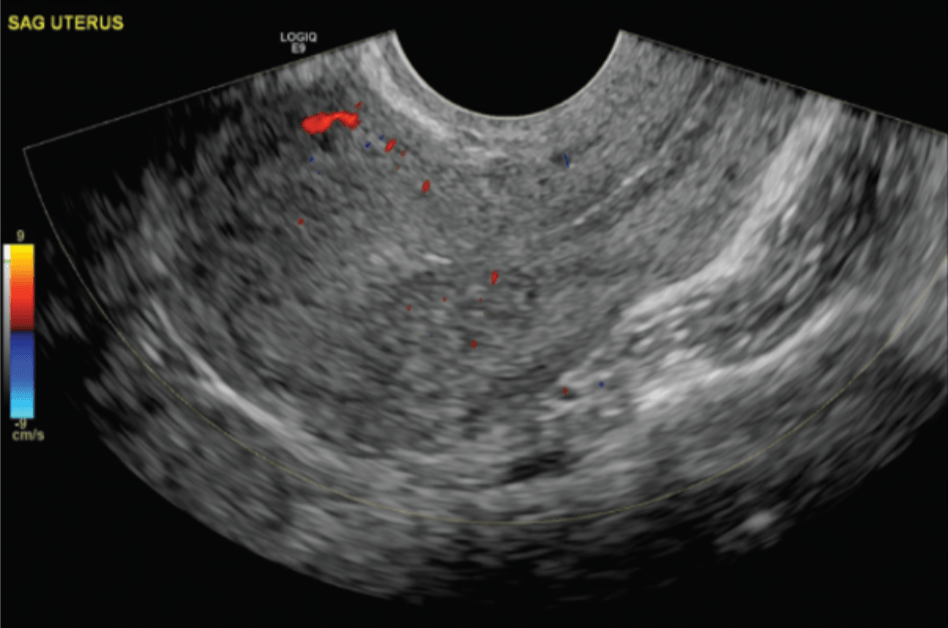

Screening Whole Body (Women)

(Carotid, thyroid, liver, abdomenal aorta, pancreas, kidneys, gallbladder, aorta, spleen, gall bladder, liver, lower legs, posterior calf, bladder, and uterus)

This screening can help identify abnormalities such as tumors, cysts, or vascular issues at an early stage, potentially improving treatment outcomes. Our general screening exams include: breast, thyroid, kidneys, liver, spleen, aorta, pancreas, and calf veins.

Additional screening may include prostate and uterus.